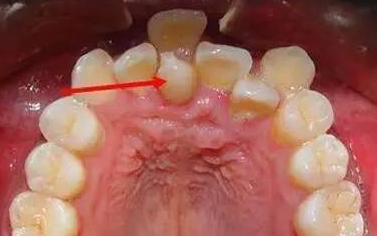

「成年人乳牙滯留需要脫牙嗎?」深圳牙醫為大家科普,以下系治療建議:

1. 先檢查呢個位置嘅恒牙萌出冇,如果萌出,就掹掉滯留嘅乳牙。

2. 如果冇萌出,就拍x線片檢查,呢個位置有冇恒牙,如果有恆牙,形態正常,可以牽引輔助萌出,就掹掉滯留嘅乳牙。

3. 如果冇萌出嘅恒牙,形態畸形,或阻生位置深,唔得牽引輔助萌出,或根本就缺失恒牙,而且,乳牙牙根冇吸收,就保留乳牙。

4. 如果恒牙難以萌出,或形態畸形,或根本就缺失恒牙,而且乳牙牙根吸收,就掹掉乳牙,做種植牙或牙冠修復。